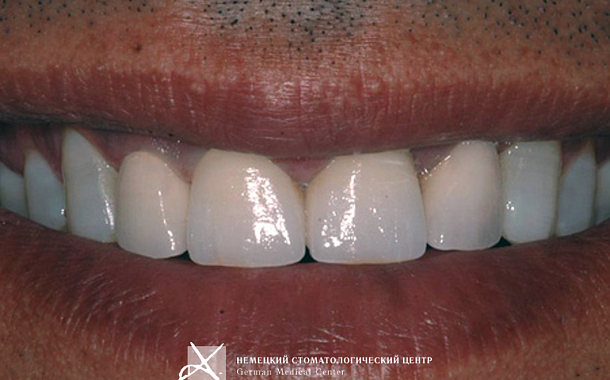

- Визуализация результатов: Пациенты могут увидеть предполагаемый результат лечения еще до его начала, что помогает в принятии информированных решений.

- Максимально точные и эстетичные ортопедические конструкции